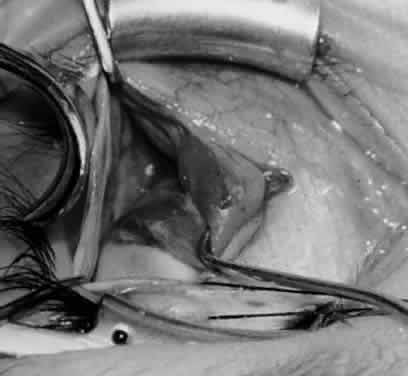

Fig. 12. An Aebli scissor is placed beneath the inferior oblique muscle insertion before it is sectioned from the globe.

Fig. 13. The inferior oblique muscle is sectioned from the globe. A preplaced 6-0 Vicryl suture is attached to the insertion.

Fig. 14. The inferior temporal vortex vein, 8 mm posterior to the temporal insertion of the inferior rectus muscle, is held on a Green muscle hook.